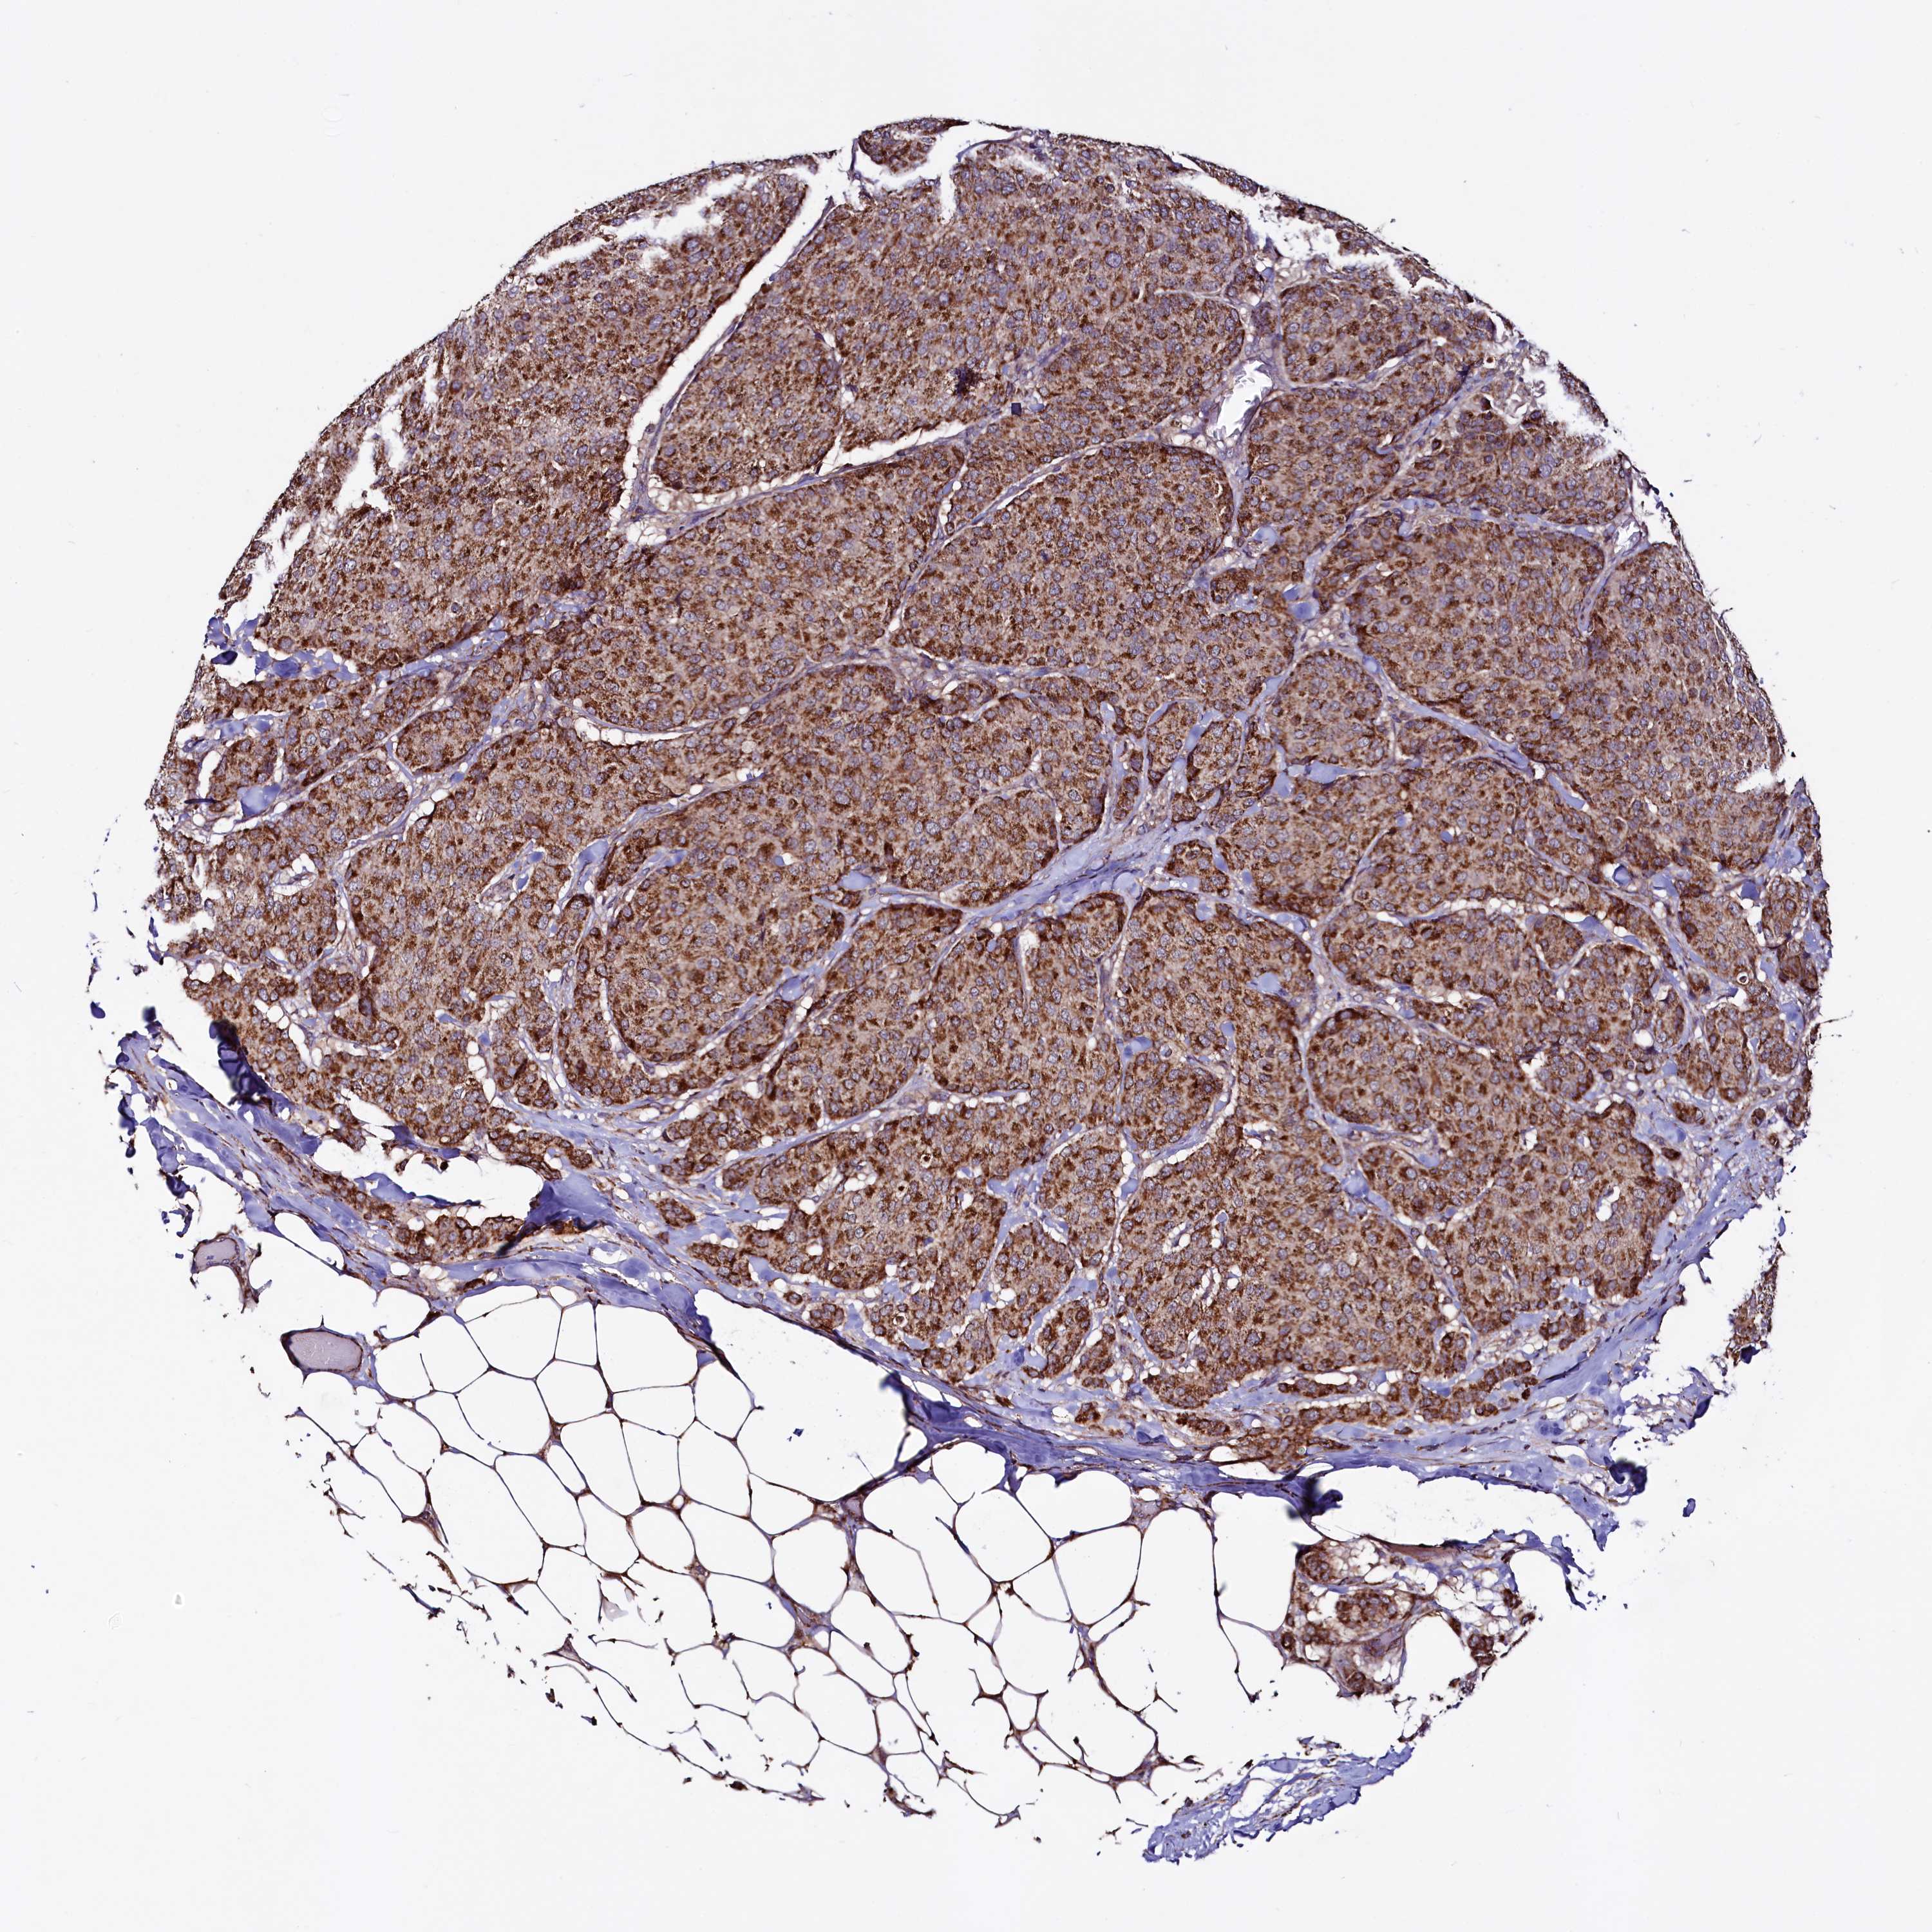

BRCA TCGA BRCA VALIDATION PROTEIN EXPRESSION